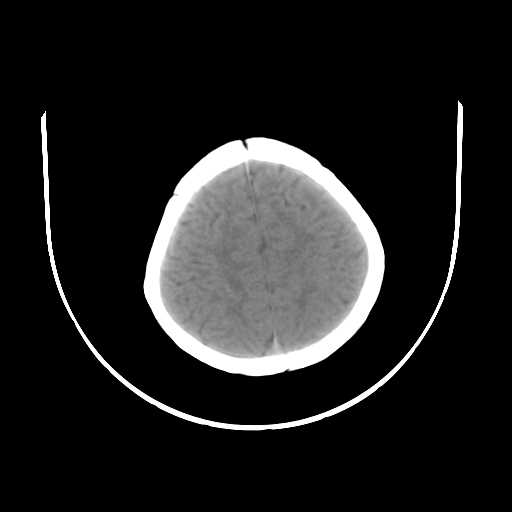

女,10个月,头外伤三天,伤后爱哭闹,吃奶少,睡觉不踏实。

左侧颞极蛛网膜囊肿

1)左侧颞极蛛网膜囊肿。2)第四脑室出血?

1、左侧颞极蛛网膜囊肿;2、第四脑室出血?3、右侧顶叶脑裂畸形伴灰质异位?